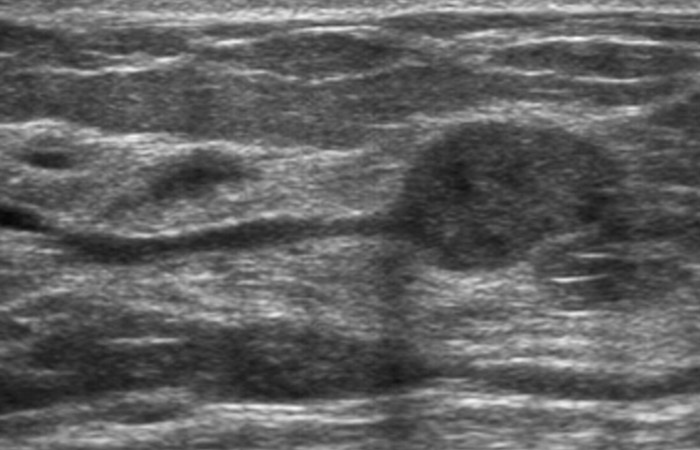

Το υπερηχογράφημα μαστών αποτελεί συμπληρωματική προς τη μαστογραφία εξέταση και δεν την υποκαθιστά, ιδίως σε γυναίκες άνω των 40 ετών.